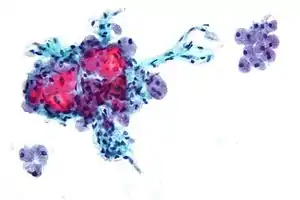

Micrograph of a Hurthle cell neoplasm.

Hurthle cell thyroid cancer is often considered a variant of follicular cell carcinoma.[2][3] Hurthle cell forms are more likely than follicular carcinomas to be bilateral and multifocal and to metastasize to lymph nodes. Like follicular carcinoma, unilateral hemithyroidectomy is performed for non-invasive disease, and total thyroidectomy for invasive disease.